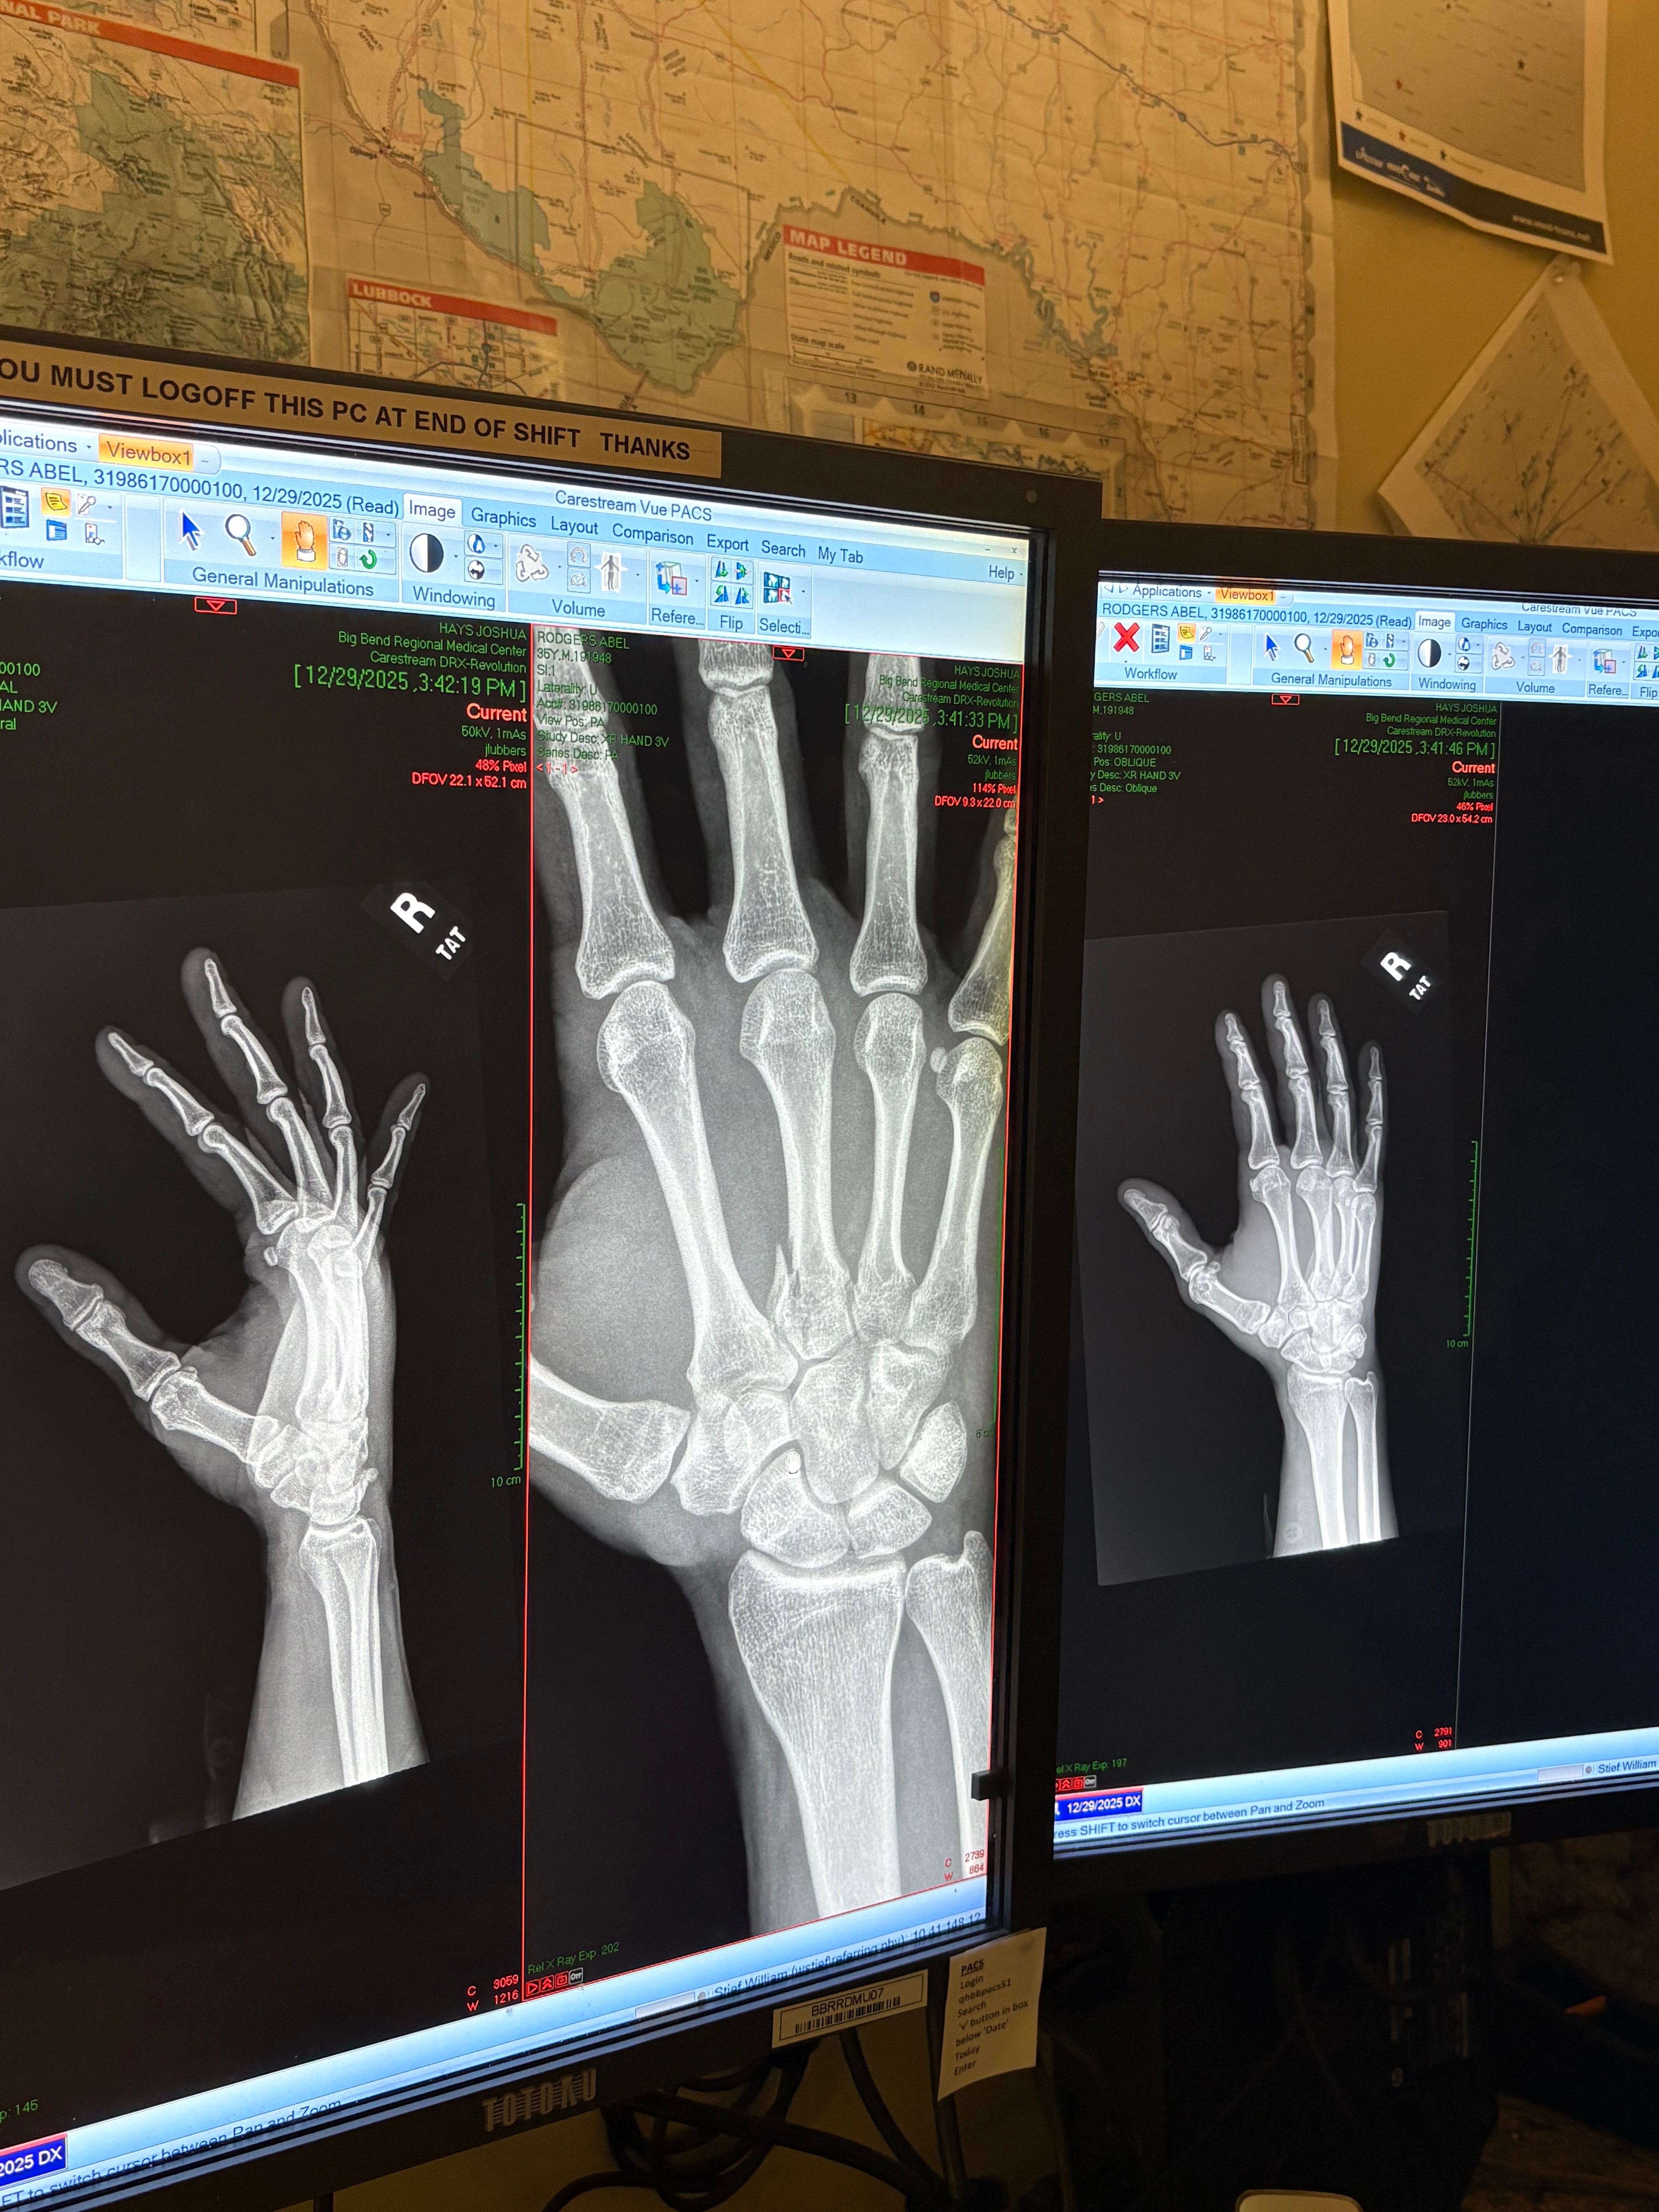

Recently, Abel sustained a serious injury to his right hand, resulting in a broken metacarpal. The injury will require surgery in order to heal properly and avoid long-term complications such as arthritis or loss of function.